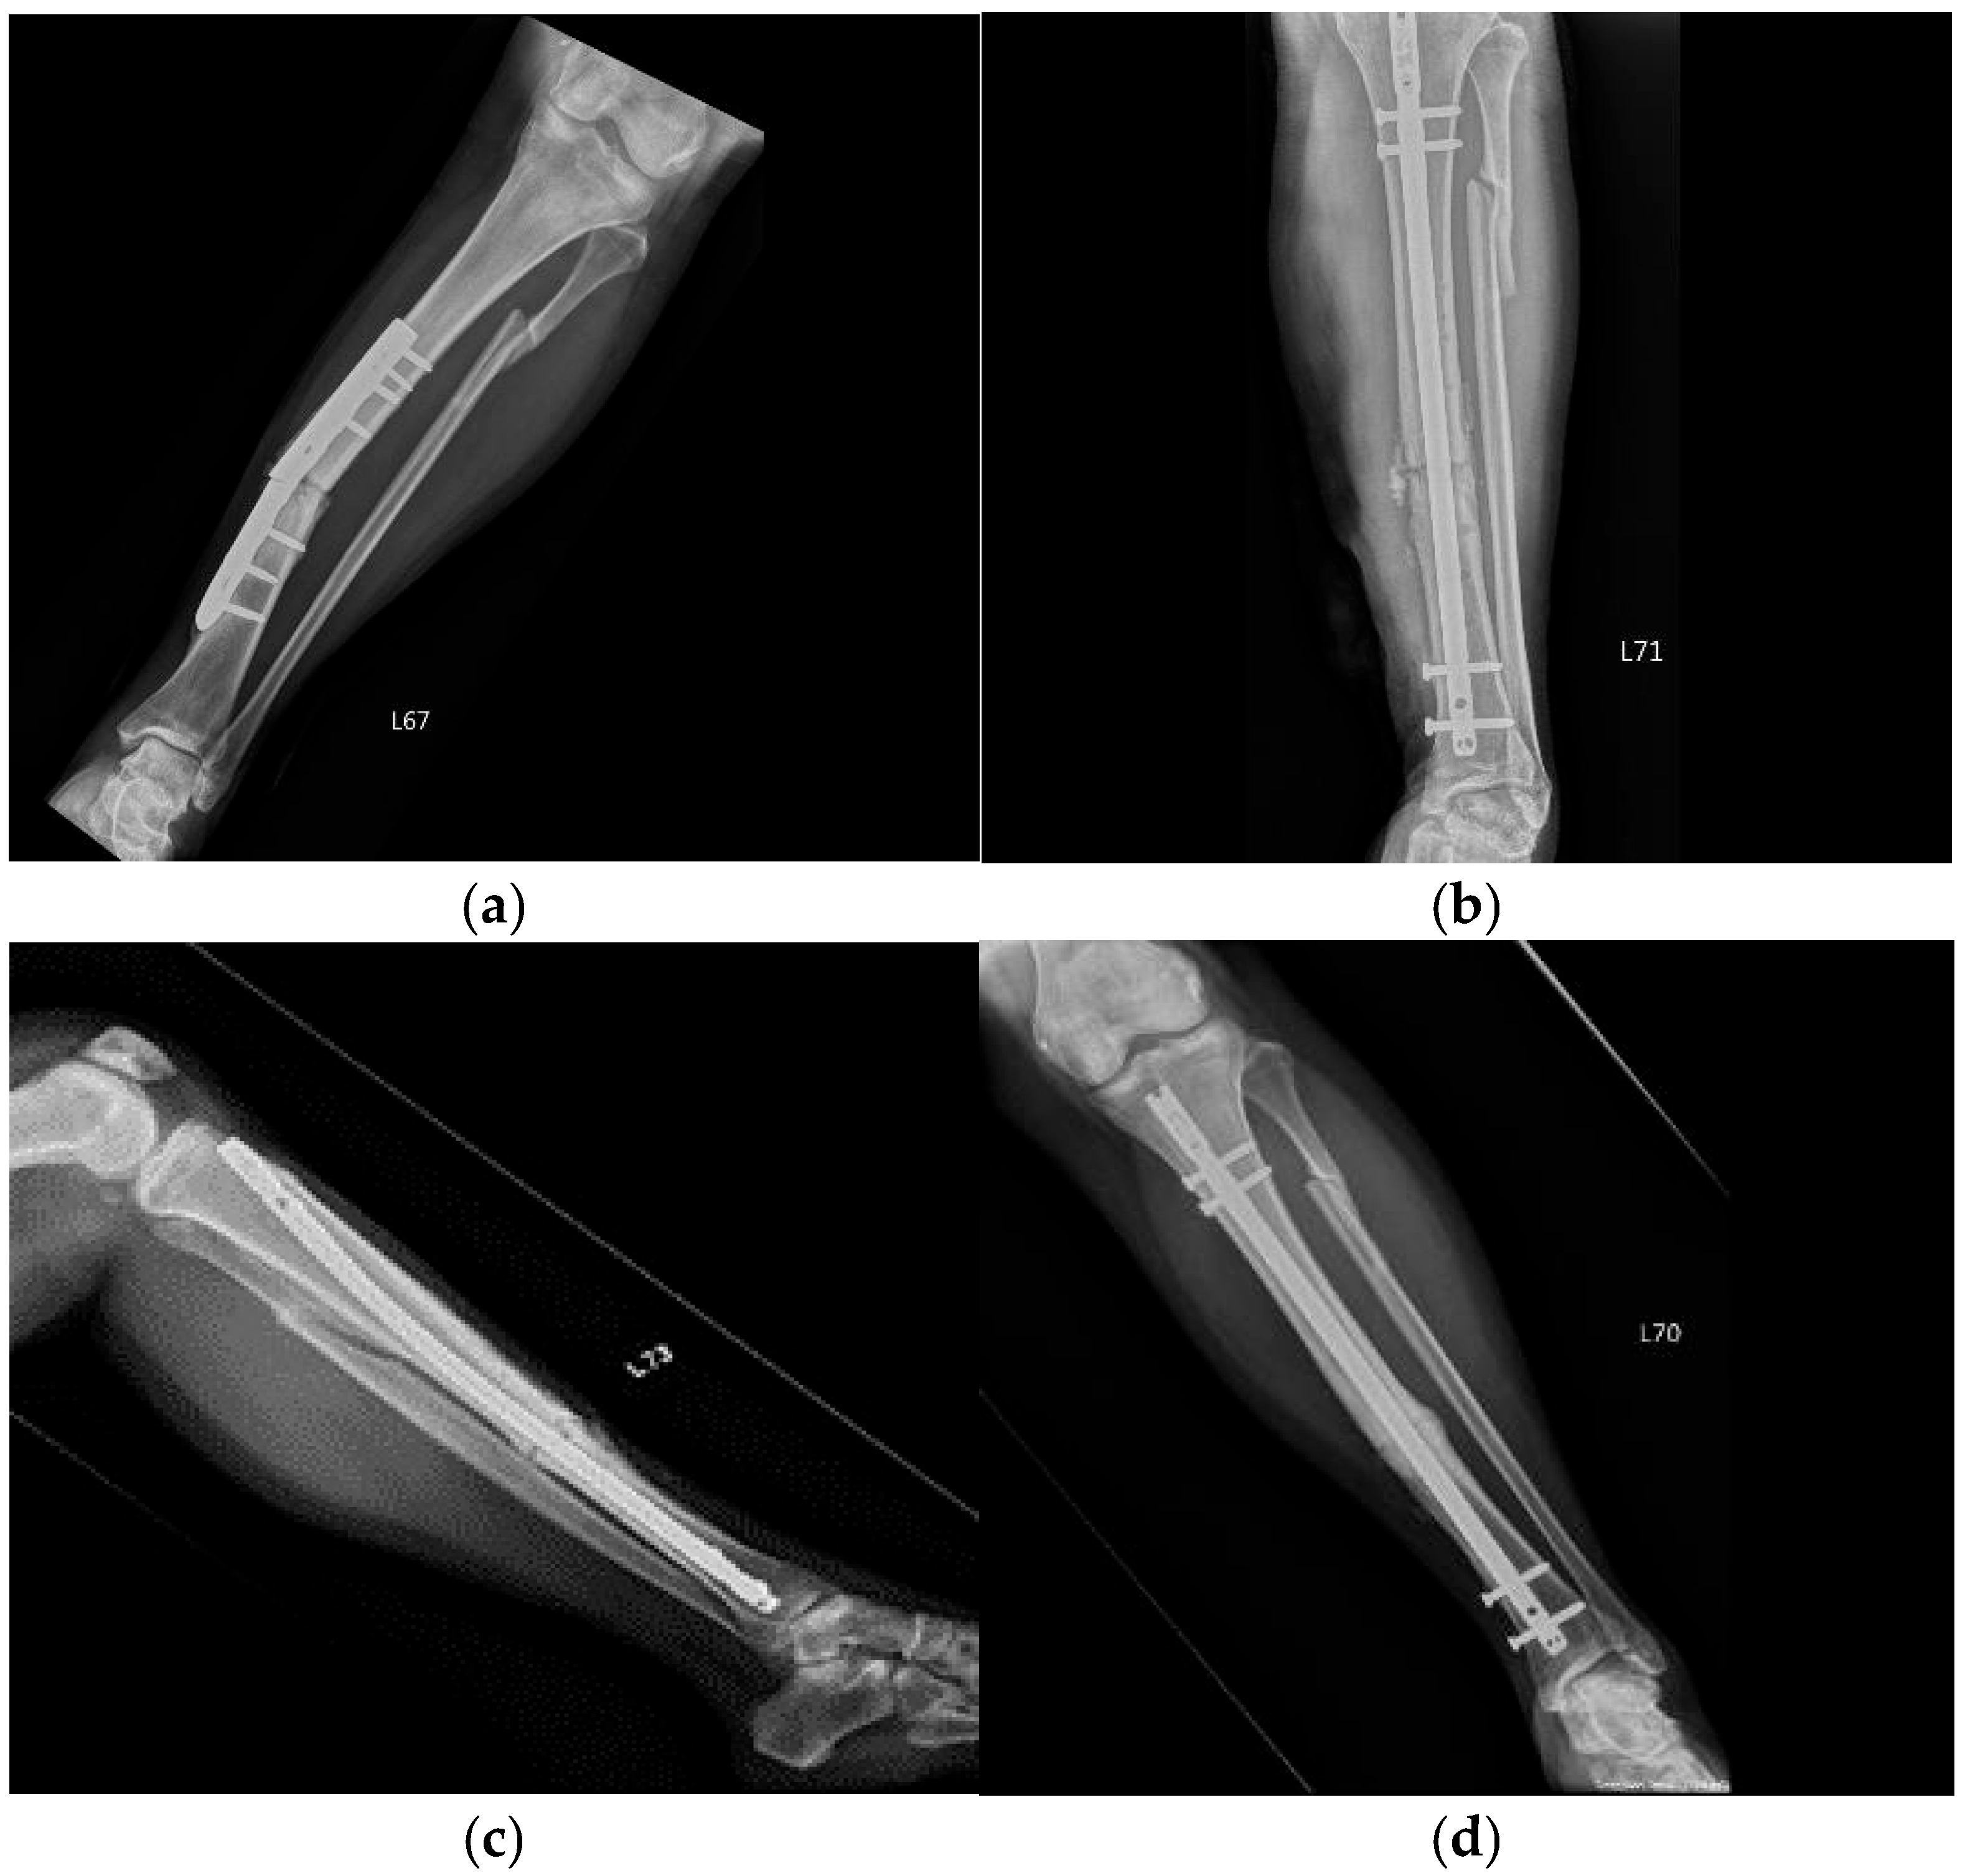

| 1 | 50 | Female | Tibial fracture | Plate implant failure, followed by intramedullary nail at 9 months but still non-union | Hypertrophic | 9 | 3 | C-arm fluoroscopy | Periosteum | 5 | 12 | Union |

| 3 | 45 | Male | Right tibia and fibula fracture | Dynamization of distal screws on tibia; ACS injection was given on fibula | Hypertrophic | 9 | 3 | C-arm fluoroscopy | Periosteum | 4 | 12 | Union |

| 10 | 21 | Female | Right upper tibia fracture | Non-union after ORIF | Bone defect | 12 | 3 | Ultrasound | Intramedullary | 4 | 6 | Union |